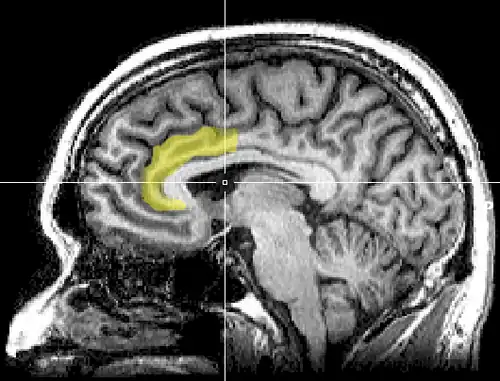

Medial surface of left cerebral hemisphere, with anterior cingulate highlighted | |

In human brains, the anterior cingulate cortex (ACC) is the frontal part of the cingulate cortex that resembles a "collar" surrounding the frontal part of the corpus callosum. It consists of Brodmann areas 24, 32, and 33.

Anatomy

The anterior cingulate cortex can be divided anatomically based on cognitive (dorsal), and emotional (ventral) components.[5] The dorsal part of the ACC is connected with the prefrontal cortex and parietal cortex, as well as the motor system and the frontal eye fields,[6] making it a central station for processing top-down and bottom-up stimuli and assigning appropriate control to other areas in the brain. By contrast, the ventral part of the ACC is connected with the amygdala, nucleus accumbens, hypothalamus, hippocampus, and anterior insula, and is involved in assessing the salience of emotion and motivational information. The ACC seems to be especially involved when effort is needed to carry out a task, such as in early learning and problem-solving.[7]